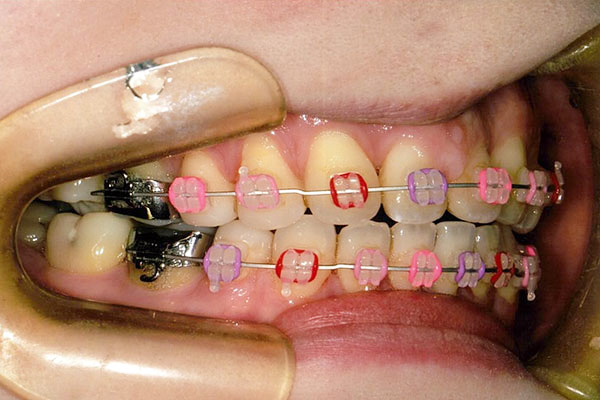

6ヶ月後